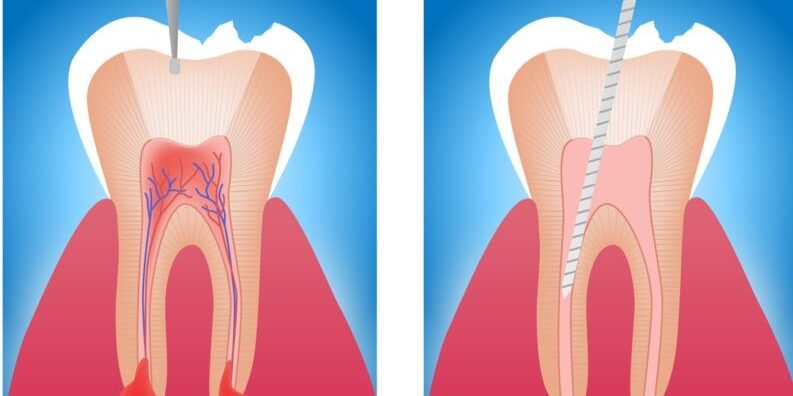

A Importância da Limpeza Dentária Você sabe de quanto em quanto tempo é necessário fazer a limpeza dentária? Este procedimento simples também conhecido como profilaxia bucal deve ser realizado com uma certa periodicidade para manter o seu sorriso bonito, saudável e livre de doenças. Nós últimos temos a prevenção odontológica tem sido muito procurada para…